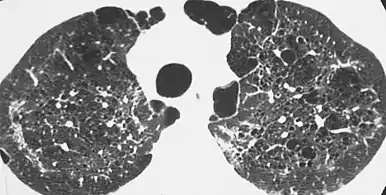

High-resolution computed tomography (HRCT) showing ground-glass attenuation with a geographic or mosaic distribution.[7]

HRCT of cysts of pneumocystis pneumonia. These are usually multiple and bilateral, but range in size, shape and distribution.[7]